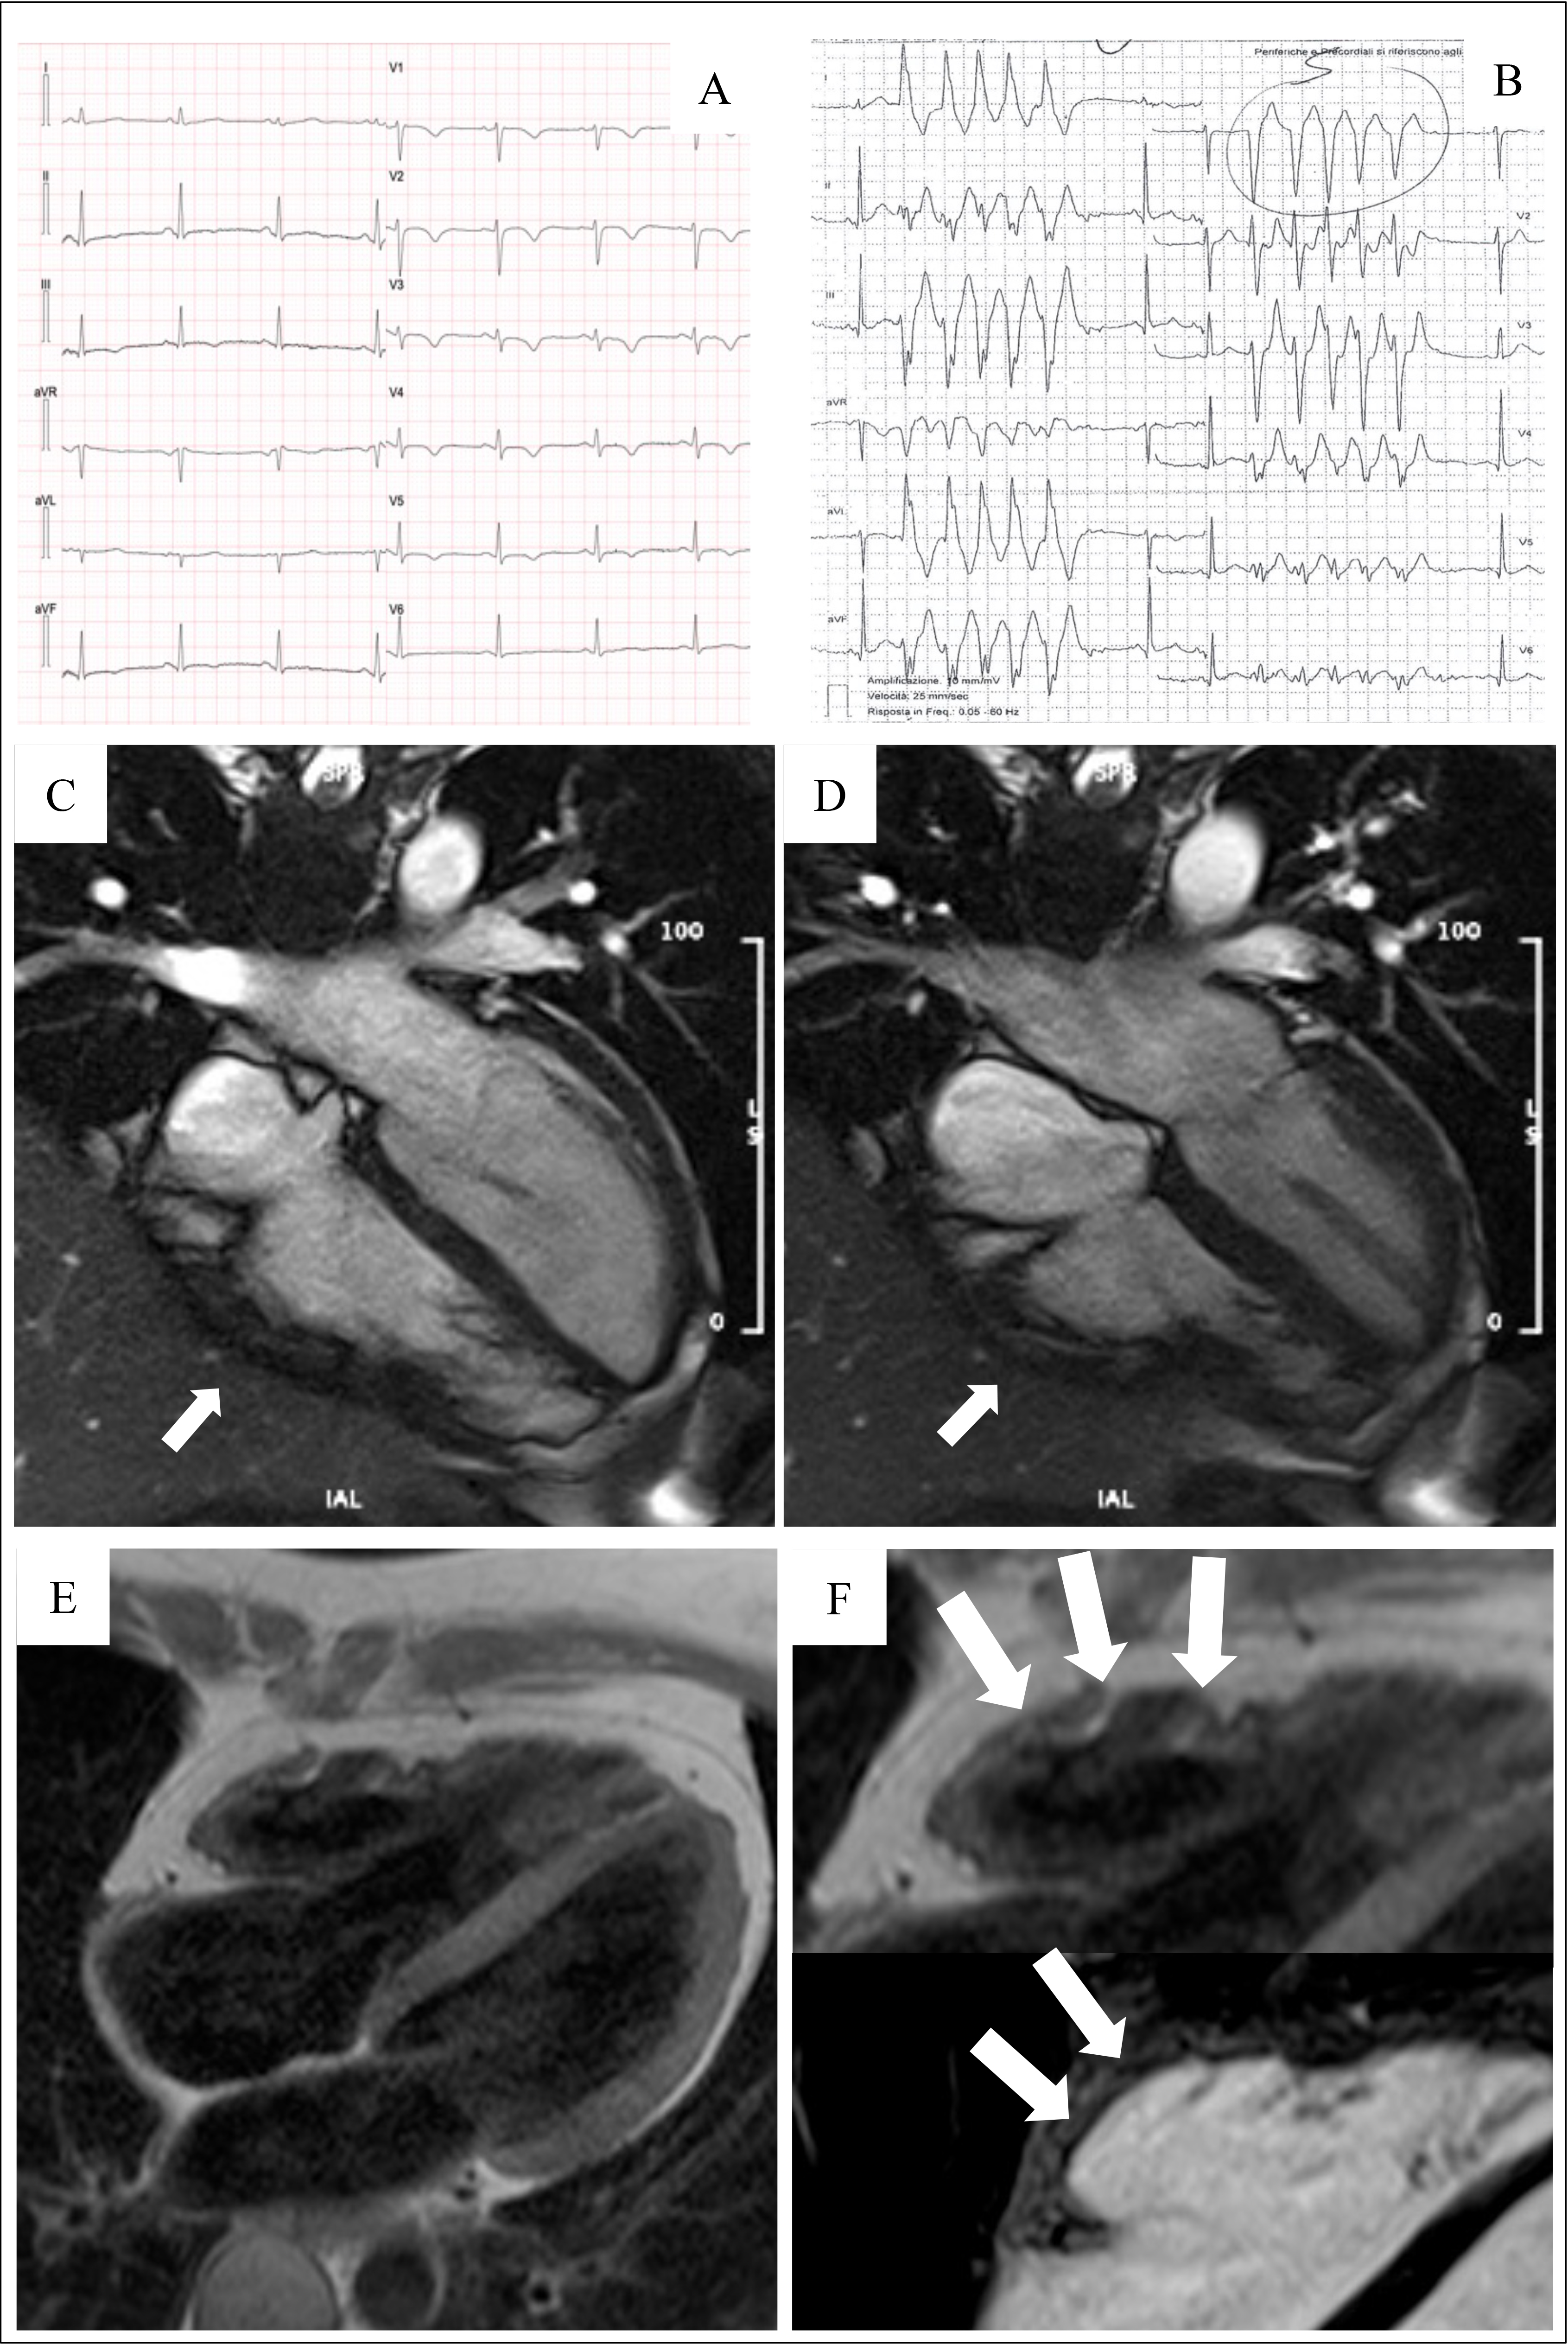

The introduction of non-invasive tissue characterization with CMR is one of the most important innovations of the 2020 criteria. The major CMR criterion is the presence of transmural LGE in at least 1 RV segment, confirmed in 2 orthogonal views. Currently, the diagnostic specificity of RV LGE is considered high, instead the sensitivity is low. This is due to the CMR technology characterized by a poor spectral resolution and suboptimal contrast/noise ratio in quantifying the thin RV wall [17, 28, 29, 30]. The highest specificity is reached when wall motion abnormalities and pre/post contrast signal alterations are considered together [29] (Fig. 3, Ref. [31]).

Fig. 3.

Fig. 3.Clinical features of ARVC. Basal ECG, exercise testing ECG and CMR findings in a 38-year-old woman hospitalized for sustained VT. Basal ECG showed TWI in V1–V5 and flattened T wave in inferior leads (A). Exercise testing revealed frequent PVBs and a non-sustained VT with LBBB/superior axis morphology, originating from RV free wall (B). CMR revealed mild RV dilatation, moderate RV systolic disfunction, a wide peritricuspid aneurysm, with an extreme thinning of the wall (four-chamber cine view in diastolic phase, C, and systolic phase, D). The PD-TSE sequences revealed fatty infiltration of the RV wall, especially in the subtricuspid region (E, and magnified on the top of F). No RV LGE was identified, not even in the same regions of RV fatty infiltration, maybe because an extreme thinning of the RV wall (F on the bottom). The diagnosis was “definite ARVC”. ARVC, arrhythmogenic right ventricular cardiomyopathy; CMR, cardiac magnetic resonance; LBBB, left bundle branch block; LGE, late gadolinium enhancement; PD-TSE, positron density-turbo spin echo; PVBs, premature ventricular beats; RV, right ventricle; TWI, T wave inversion; VT, ventricular tachycardia. Adapted from Graziano et al. [31].